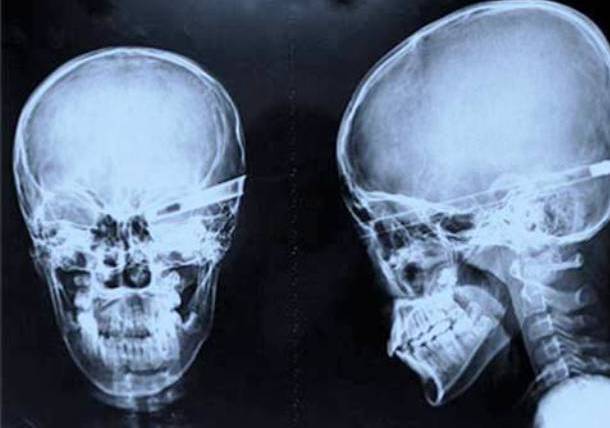

4. A Near Fatal Robbery Defence

This looks fatal - a knife right through the skull right down, reaching the eye socket. This happened when some young men tried to stop a robbery back in 2008. This happened as a result of one of the robbers launching the knife into his head. Thankfully he survived and somehow fully recovered.Advertisement